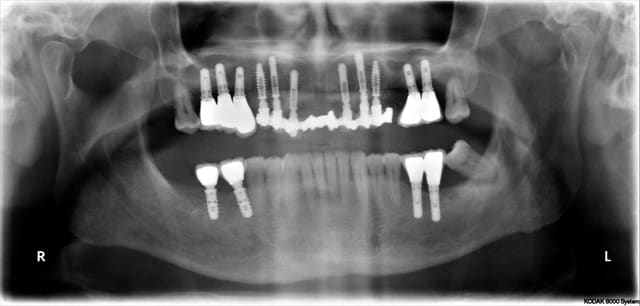

Pour être précis je dirais que l'implant en 27 et non pas 26 n'a jamais été vraiment bien

Mais parle moi donc plutôt du résultat en 46 47 qui sont dans la même bouche avec le même terrain paro

Simple question, pourquoi conserver les dents postérieures (28-38, je pense) qui sont en phase finale de paro ?

L'implant 27 devrait aussi être remplacé, enfin, selon ce qu'on voit sur les images montrées.

Il y avait 9 implants avant la chir 1 va mal et tous vous focalisé, amusant mais classique

28 n'est pas en rapport avec le problème de l'implant 27

Dans 3 mois 28 & 38 vont disparaitre, et je tenterais en même temps de sauver 27

En cas d'échec probable dans l'implant disparaitra et lors de la prothèse définitive j’intégrerais 26 ou pas